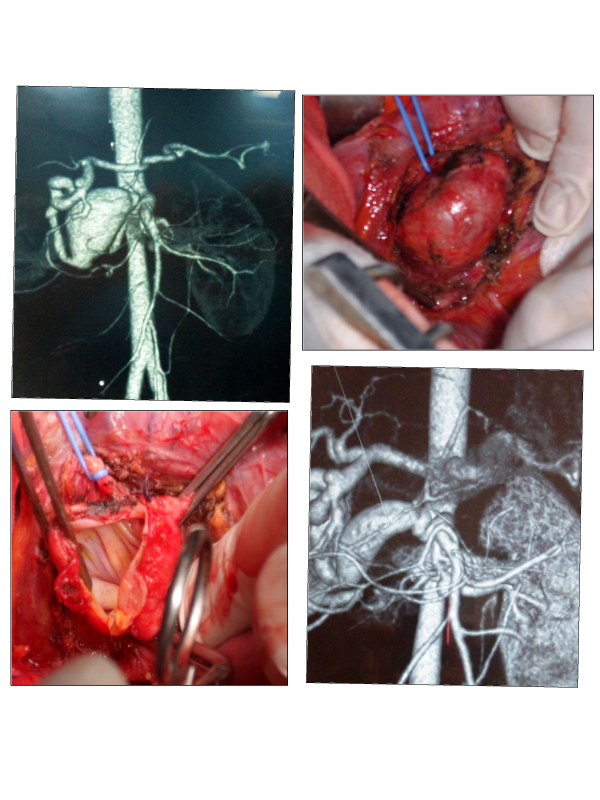

Case Presentation: R.E is a 26-year-old woman with neurofibromatosis type I (Recklinghausen’s disease) diagnosed since 5 years, and blood hypertension due to bilateral stenosis of the renal arteries, treated medically and by percutaneous angioplasty. She was admitted to surgery department complaining of abdominal pain and palpitations. The patient had no history of acute or remote trauma. Her physical examination was remarkable for the café-au-lait spotty pigmentation of the skin that is typical of patients with von Recklinghausen’s disease (Figure 1). The patient was hemodynamically stable, with a blood pressure of 144/94 mmHg and a pulse of 88 beats/min. A computed tomography scan revealed an occlusion of the celiac artery, and three non-complicated saccular aneurysms: an aneurysm arising from the duodeno-pancreatic arcade measuring 30 mm (Figure 2), an aneurysm of the splenic artery measuring 6 mm, and an aneurysm of pancreatic collateral of the superior mesenteric artery measuring 11 mm (Figure 3). The patient did not have any symptoms of bowel ischemia. So, a surgical repair under median laparotomy was decided.The largest aneurysm was dissected (Figure 4), was opened, and narrowed by an aneurysmorraphy (Figures 5 and 6). The patient made a full recovery and was discharged 4 days postoperatively. A follow-up CT scan (1 month after the procedure) showed patency of the artery without aneurysmal recurrence (Figure 7).